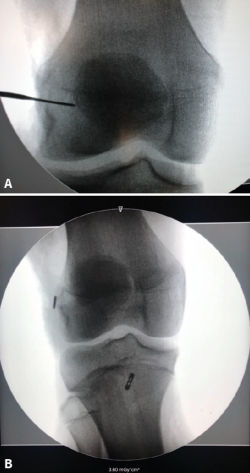

Figura 6. Imagen de radioscopia intraoperatoria de una reconstrucción del ligamento cruzado anterior (LCA) en un paciente esqueléticamente inmaduro con técnica transfisaria parcial. A: el punto de entrada del túnel femoral distal a la fisis se encuentra marcado con una punta metálica; B: control postoperatorio de técnica transfisaria parcial, en el que se observa el botón cortical del fémur en la epífisis femoral distal y el botón tibial en situación distal a la fisis, en una localización más central para realizar un túnel más vertical y disminuir el daño fisario.